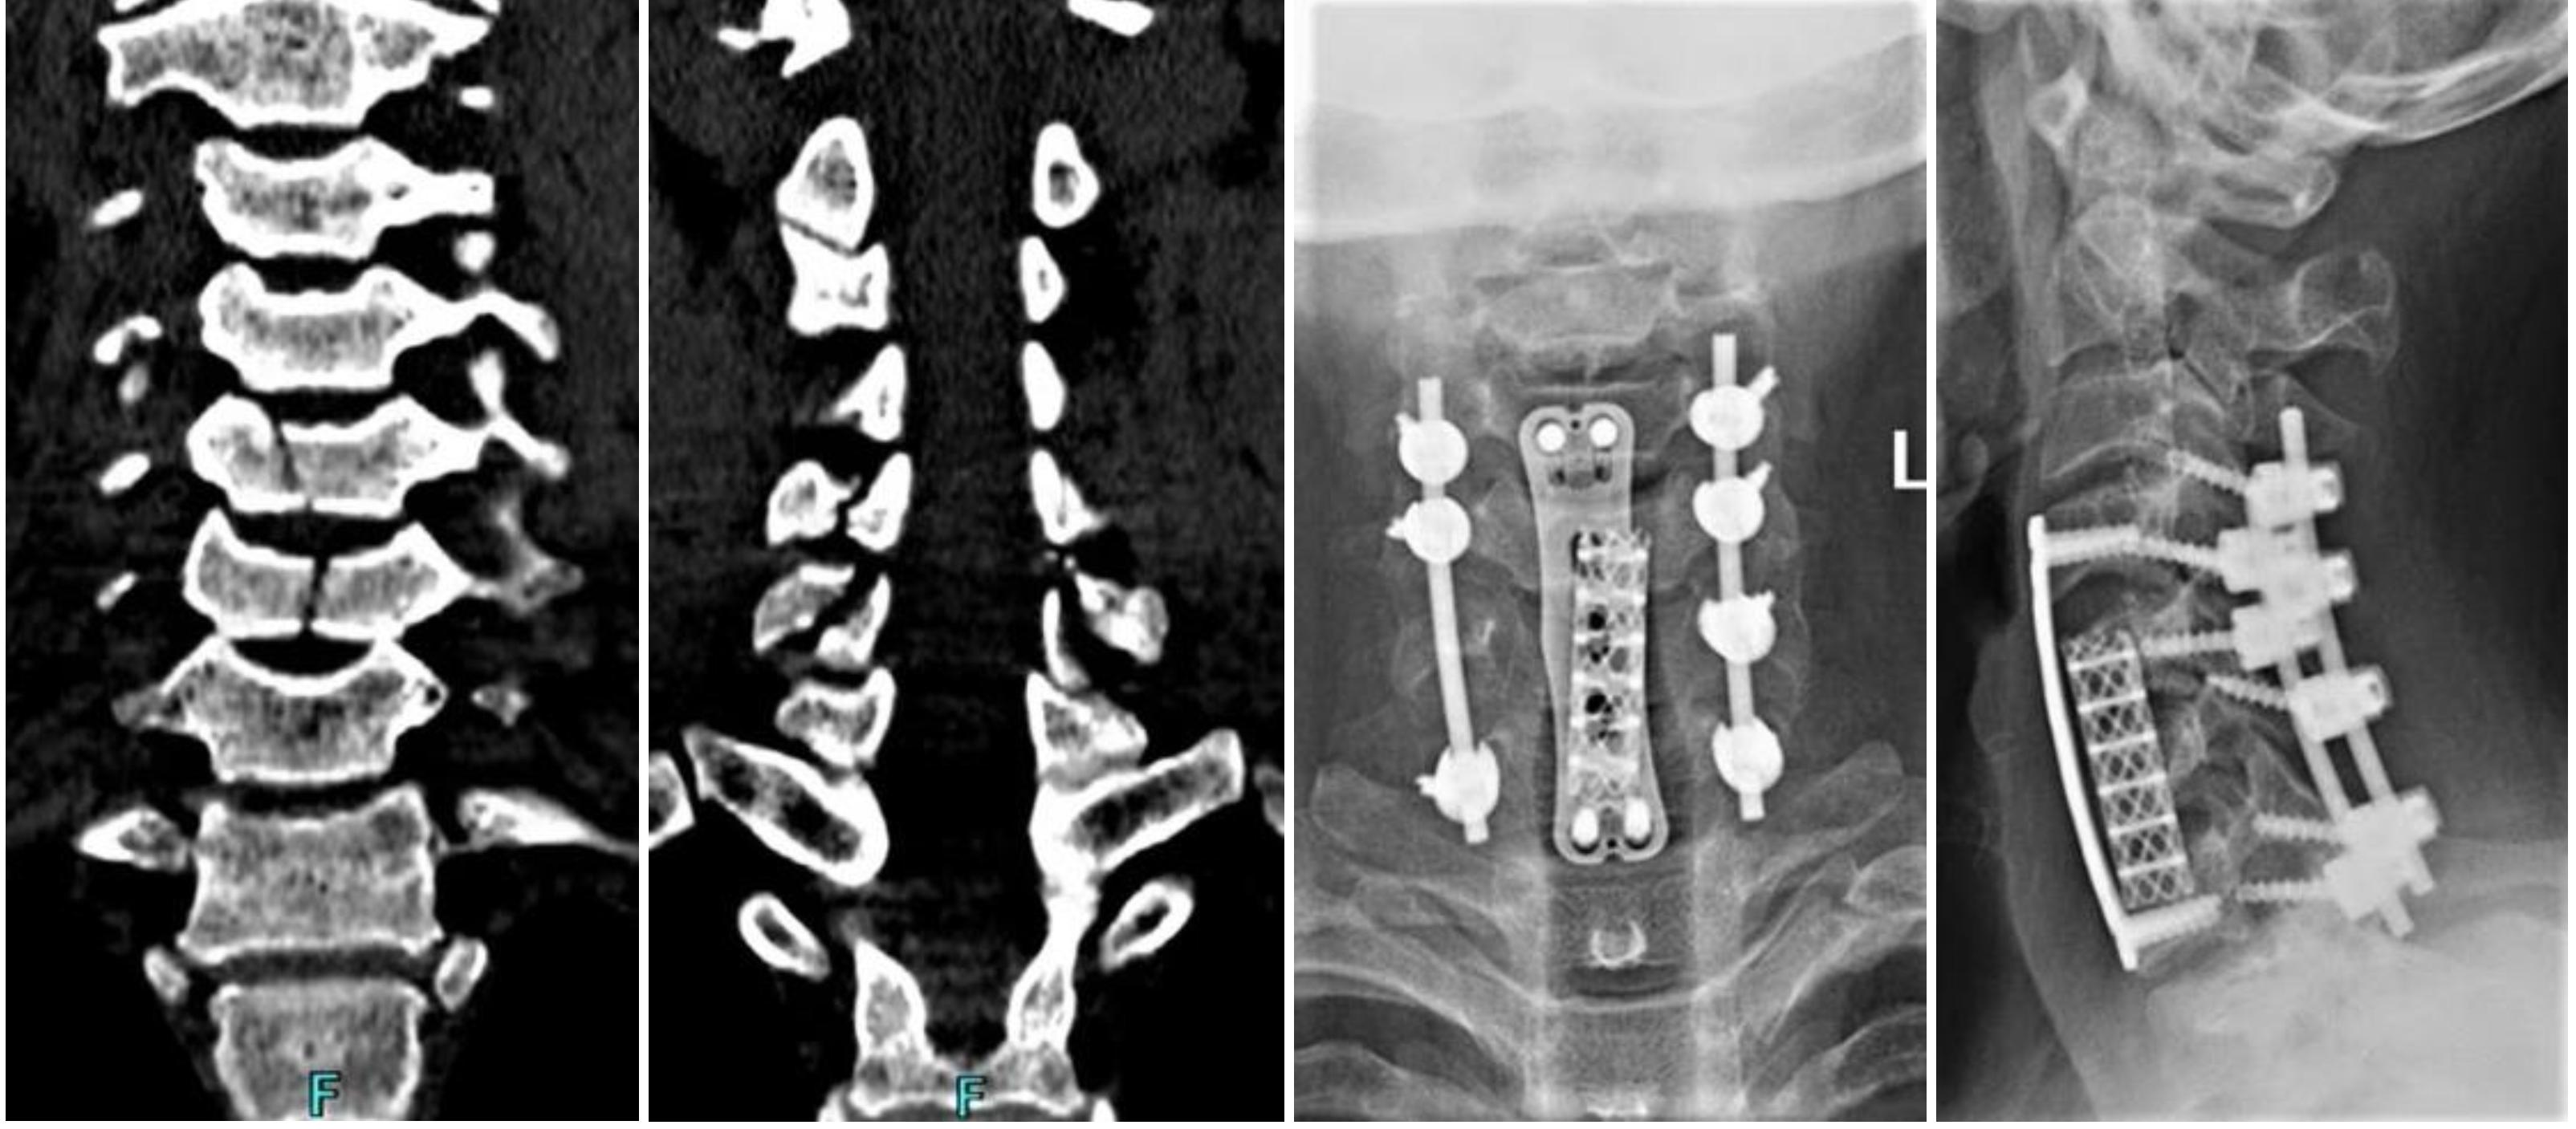

颈椎外伤后行:颈椎前路椎管减压、椎间盘切除、椎体次全切除、钛笼植入椎间融合、钢板螺钉内固定术及颈椎后路椎板切除减压、侧块螺钉内固定术